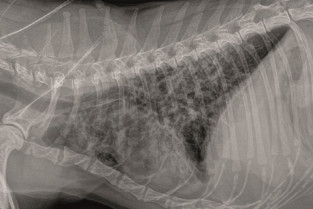

- d'interpréter des radiographies thoraciques ;

- diagnostiquer et traiter les principales entités pathologiques respiratoires : épanchements pleuraux, épanchements thoraciques, bronchopneumopathies.